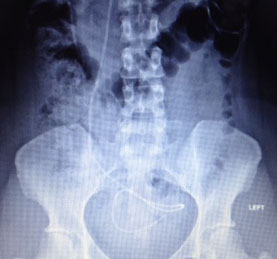

Abdomen view of current distal catheter and old catheter (far left)

Close up of distal catheter (end)

Right frontal ventriculo-peritoneal shunt is seen coursing through the right neck soft tissues, anteriorly through the chest wall, and coiling in the pelvis. Catheter fragments in the right neck soft tissues and right abdominal wall likely represent retained shunt fragments. No evidence of fracture or kink.

VP shunt catheter, as described, without evidence of fracture or

kink.